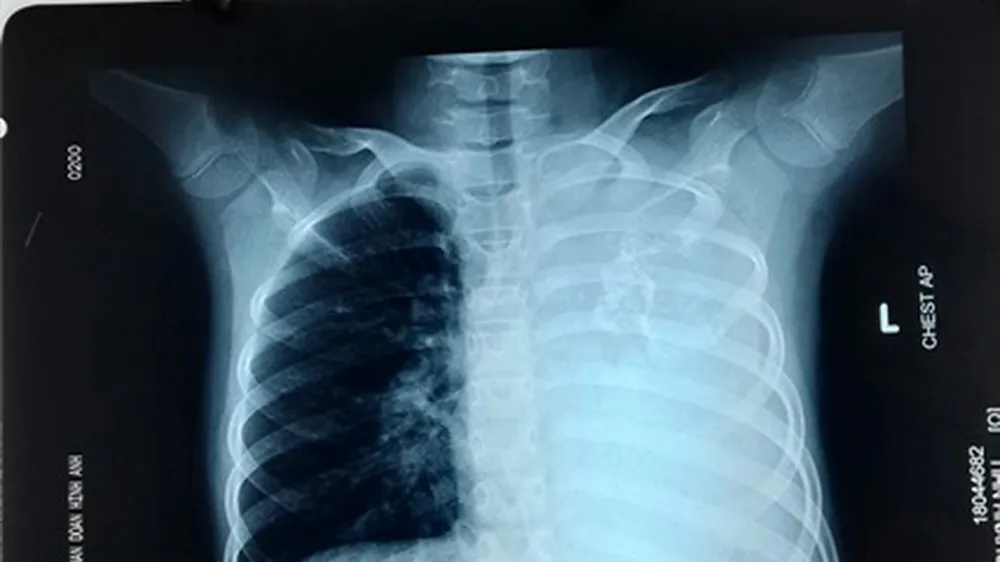

Khối u qua hình ảnh CT scan ngực

Bệnh nhi được người nhà đưa đến BV trong tình trạng ho kéo dài, khó thở khi gắng sức. Qua hình ảnh CT scan ngực, các bác sĩ đã phát hiện một khối u phổi khổng lồ.